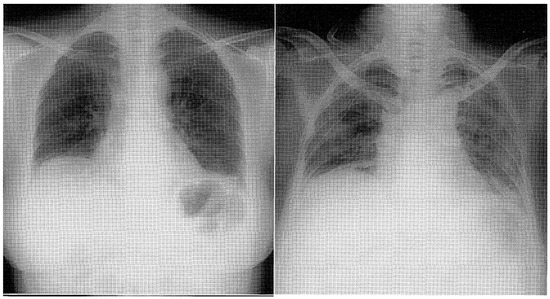

4.1. Alveolar Hemorrhage (AH)